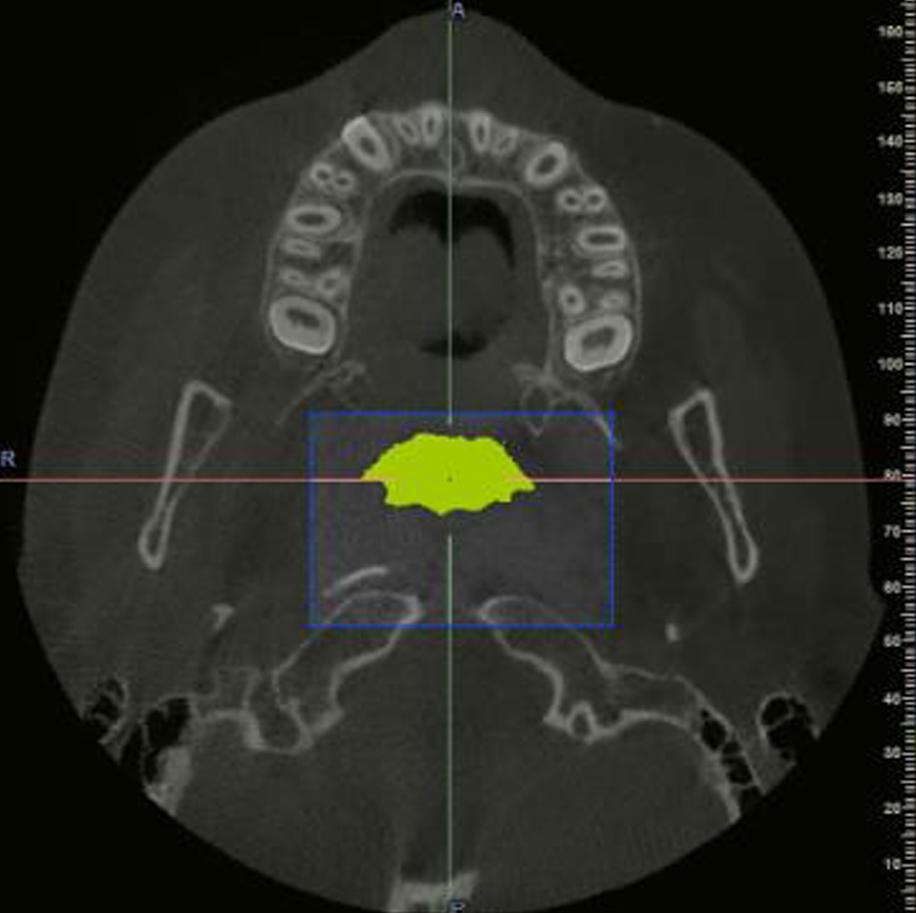

Evaluación Implantes:

Maxilar/ Mandibular/ Bimaxilar/ Orbitomaxilofacial

Estudio Localización:

Traumatismo/ Patología Ósea

Estudio Endodoncia Diente (S)